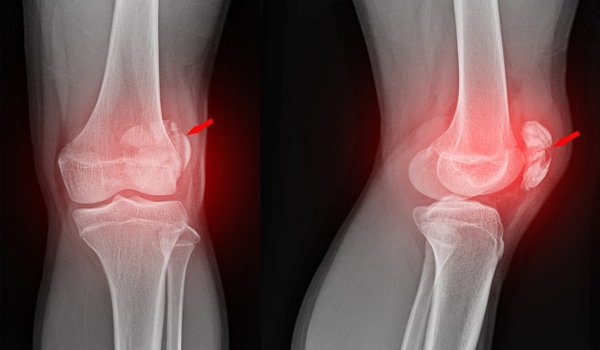

Кістки

Колінний суглоб утворюють 3 кістки: стегнова (зверху), великогомілкова (знизу) і надколінок, або колінна чашка (попереду).

Найчастіша травма — перелом. Якщо кістка ламається в області своєї головки, це може призвести до деформації поверхонь всередині суглоба, його швидкого нерівномірного зношування та інвалідизації людини.

Якщо з стегнової та великогомілкової кістками все зрозуміло, то навіщо потрібен надколінок? Надколінок утримує суглоб від зміщення кісток щодо один одного. Найчастіша проблема — вивих, усунення, перелом надколінка. Щоб його стабілізувати, застосовуються наколінники із силіконовими фіксаторами колінної чашки.